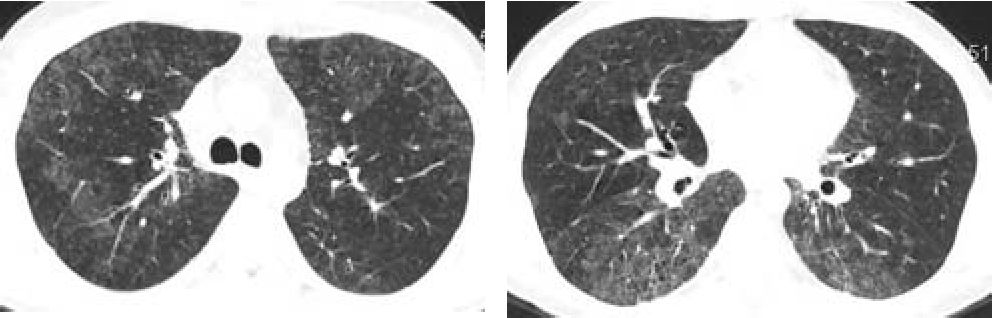

При контрольной КТ органов грудной клетки (рис. 3, 4), выполненной 06.07.2010 г. после проведенного курса лечения, отмечена значительная положительная динамика.

рис.З,4. Компьютерная томография органов грудной клетки.

Отмечается уменьшение площади и интенсивности зон «матового стекла», а также выраженности интерстициального компонента.

Таким образом, лечение глюкокортикостероидами привело к устранению анемии и существенному уменьшению выраженности хронической интерстициальной пневмонии, что подтверждено как данными КТ, так и исследованием диффузионной способности легких. Особенностью данного случая является малая выраженность поражения суставов, чем объясняются сложности своевременной постановки основного диагноза.